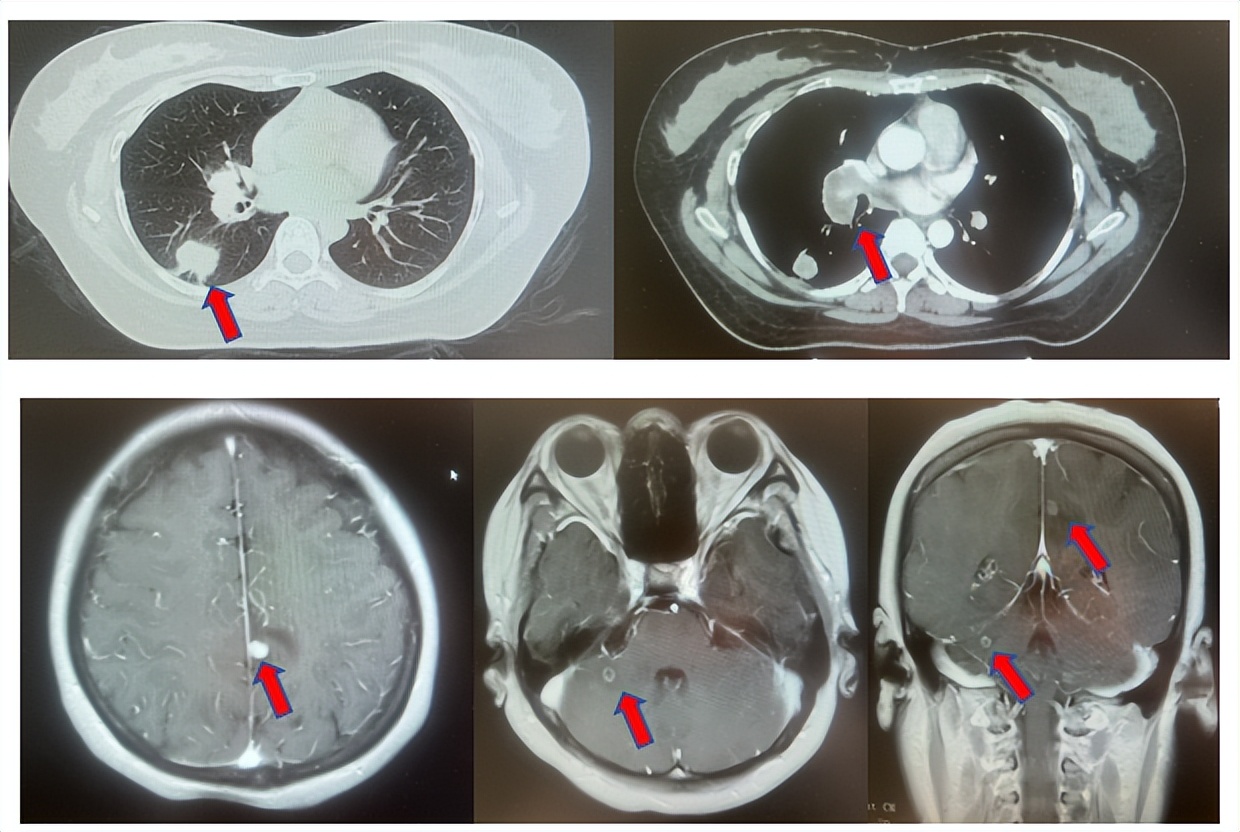

2.2影像学检查(图5)

肺+全腹CT增强:右肺中叶肿块,考虑恶性,双肺胸膜下炎症,双侧胸膜局限性增厚,右侧锁骨上淋巴结增大,纵隔淋巴结稍大;

颈部CT增强:右侧锁骨上及右颈部、纵隔多发淋巴结肿大。

图5:上两图分别展示基线时肺CT肺窗及纵隔窗右肺中叶病灶影像,下两图表示基线状态时纵隔淋巴结及锁骨上淋巴结影像。